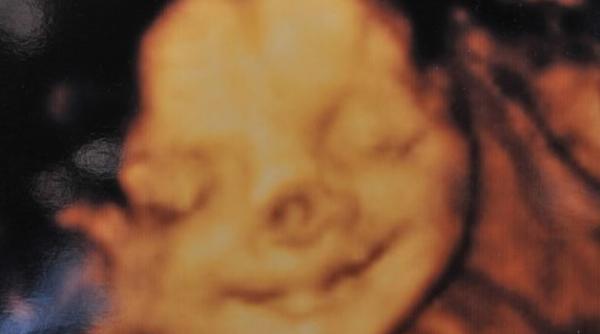

O mamă a avut parte de o surpriză INCREDIBILĂ când și-a văzut pentru prima dată fiica nou-nascută. Cum arăta micuța la naștere